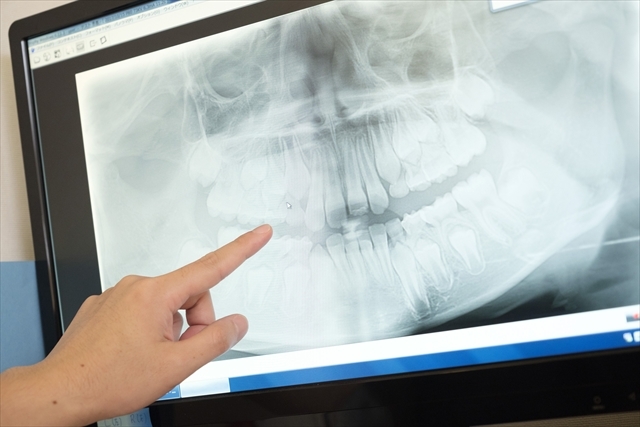

地域の毎日に

寄り添う、

歯科医療を

私たちは、ただ治療するだけでなく、

患者様の「一生の笑顔」に寄り添うパートナーを目指します。